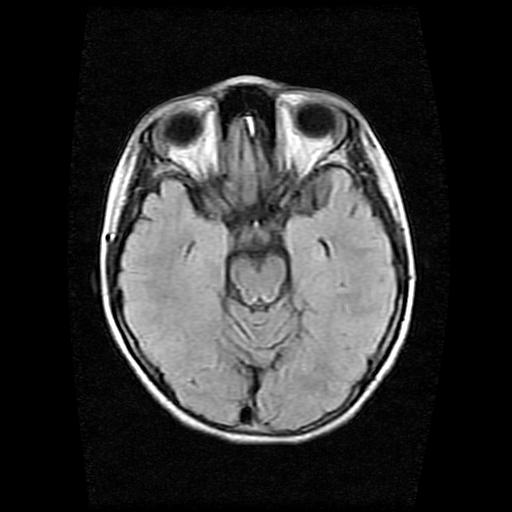

标题: PED0378:女孩9岁,癫痫,看能否停药 [打印本页]

9岁女孩,三岁时诊断为癫痫,一直服丙戊酸钠,现患者一般情况良好,家长复查核磁片,看能否停药..

巨脑回